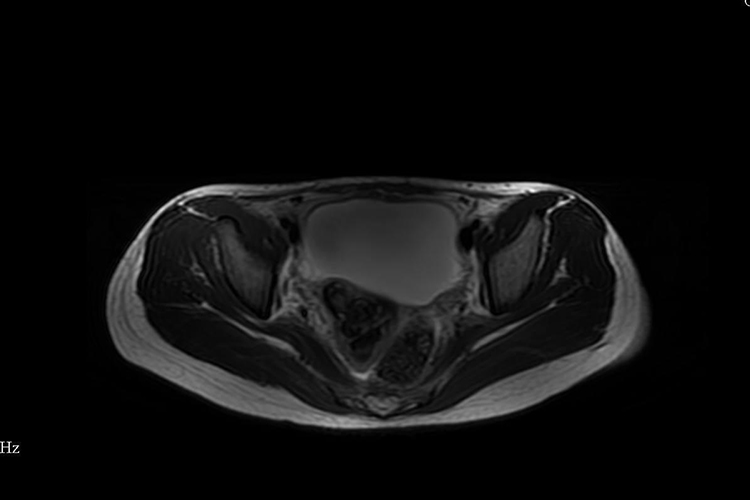

1、生理性盆腔积液:根据患者临床表现,影像学检查CT、MRI表现为水样密度/信号量较少,排卵后液体较多,盆腔各器官均无异常改变,可明确诊断。

2、病理性盆腔积液:根据患者临床表现,出现下腹痛、腰骶痛,腰酸等。影像学检查病理性盆腔积液量较生理性盆腔积液多,少量时多位于病变周围或包裹于某部位,液体因含成分不同,CT密度或MRI信号可有不同,同时可见腹膜和盆腔脏器病变,可明确诊断。